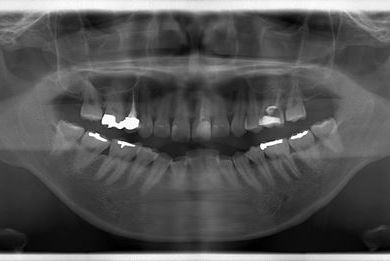

性別/年齢 女性 / 26歳

主訴 虫歯や汚れの治療を希望。

治療方針 セラミック治療にて、審美的回復を行う。

治療内容 メタルボンドセラミッククラウン1本(メタルボンド用土台1本)

総治療費 132,038円

治療期間 1年1ヶ月